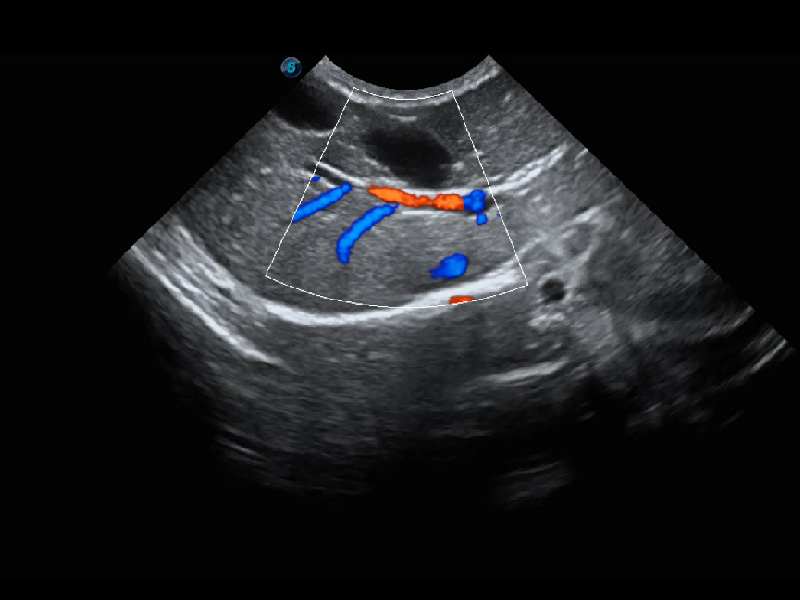

ProPet 60 作为一款高端台式动物超声设备,为动物医生的日常诊断提供了一系列贴合动物临床需求、解决临床实际问题的高级成像功能。凭借全系列高清探头,满足医生对腹部、心脏、生殖、浅表、肌骨等成像的所有需求,切实帮助您提升检查效率,提高诊断信心。

动物是人类最亲密的朋友和最值得信赖的伙伴。狗万官方网站也一直致力于探索动物专用的超声影像解决方案。 全新推出的ProPet系列,是狗万官方网站在动物超声影像智能化、专业化、精准化的一次跨越式革新。动物不能用言语来表述自己的不适,通过超声影像,ProPet系列搭建了动物医生与不同物种沟通的“桥梁”,为动物医生注入了“治愈之力”。